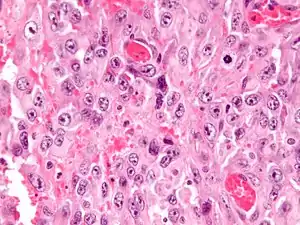

Histologically, epithelioid sarcoma forms nodules with central necrosis surrounded by bland, polygonal cells with eosinophilic cytoplasm and peripheral spindling.[3] Epithelioid sarcomas typically express vimentin, cytokeratins, epithelial membrane antigen, and CD34, whereas they are usually negative for S100, desmin, and FLI1 (FLI-1).[3] They typically stain positive for CA125.[4]

Intermed. mag.

High mag.

High mag. (SMARCB1)